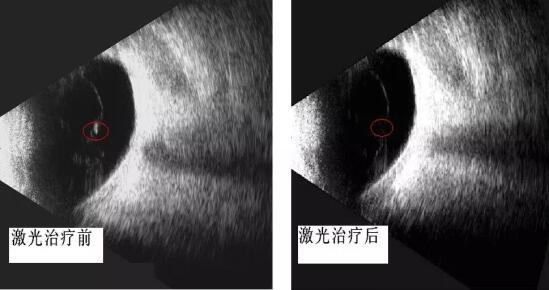

探花av 眼科开启"灭蚊"时代 ――飞蚊症的治疗